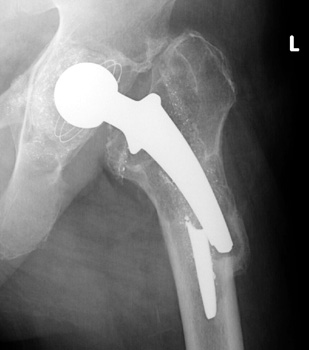

Phalanged acetabular cup with interval fracture of the medial phalange. Note progressive osteolysis in Gruen zone 7